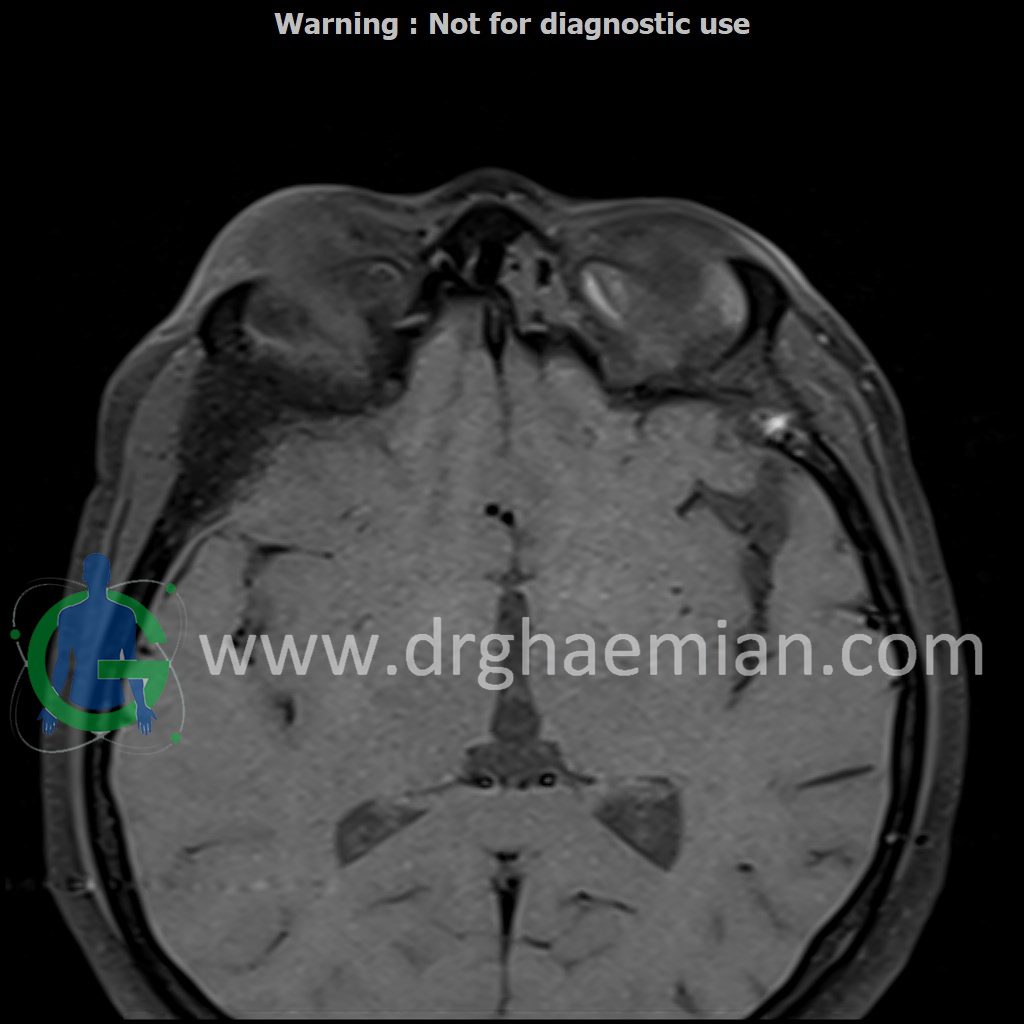

ام آر آی اوربیت با استفاده از آهنربا و امواج رادیویی تصاویری از اوربیت ها، اعصاب، عضلات و بافت های اطراف آن ایجاد می کند. در این کیس مننژیوم مغزی در پشت چشم بیمار دیده میشود.

Technique : Axial T1 , Axial , sagittal , coronal FSE T2 , coronal T1, sagittal fat sat T2 , Axial , sagittal T1 post Gd .

thickening of posterolateral of right orbit wall ( low T1/T2/STIR ) with mass effect on right temporal pole & right orbital content/proptosis , with adjacent dural thickening & post contrast enhancement ( 33x41mm – without significant change to prior MRI – 1403/09/20) suggestive for :

1.meningioma

2.fibrosis plasia with dural thickening & less probably sclerotic bone metastasis